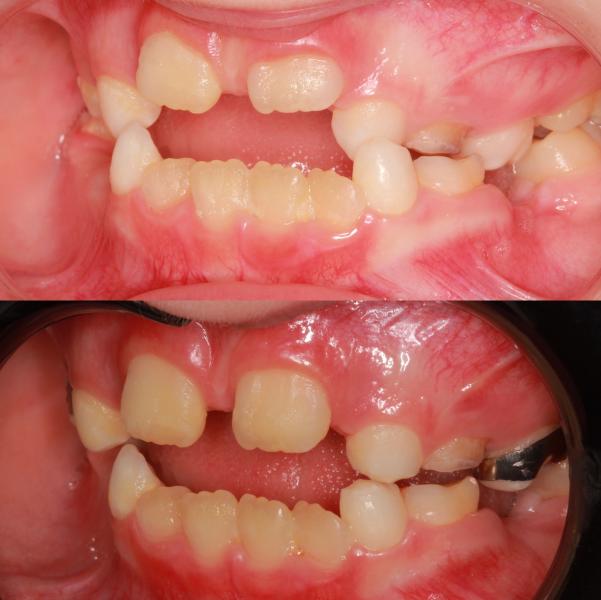

Ребёнок 👧🏼 А 7,5 годиков 🐥😹.

Жалобы родителей «Зубы не прорезываются, неправильный прикус, ассиметрия нижней челюсти».

Лечение решила проводить на несъёмной технике с помощью аппарата #маркоросса

Какие изменения мы получили в ходе расширения верхней челюсти ?